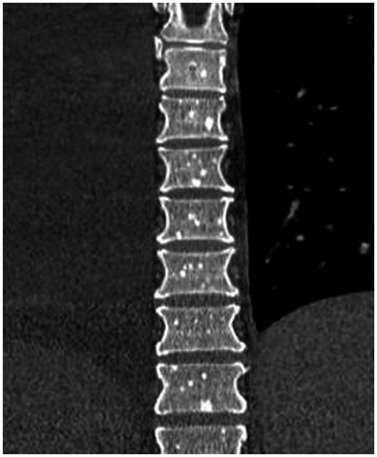

Figure